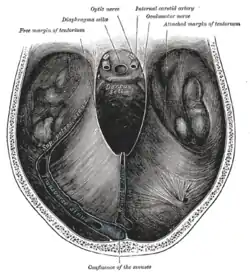

Dural veins. (Transverse sinuses labeled as "SIN. TRANS." at center right.) | |

The transverse sinuses are formed by the tentorium cerebelli and drain into the right and left sigmoid sinuses. | |

Left parietal bone. Inner surface. Dura mater and its processes exposed by removing part of the right half of the skull, and the brain

Dura mater and its processes exposed by removing part of the right half of the skull, and the brain The sinuses at the base of the skull